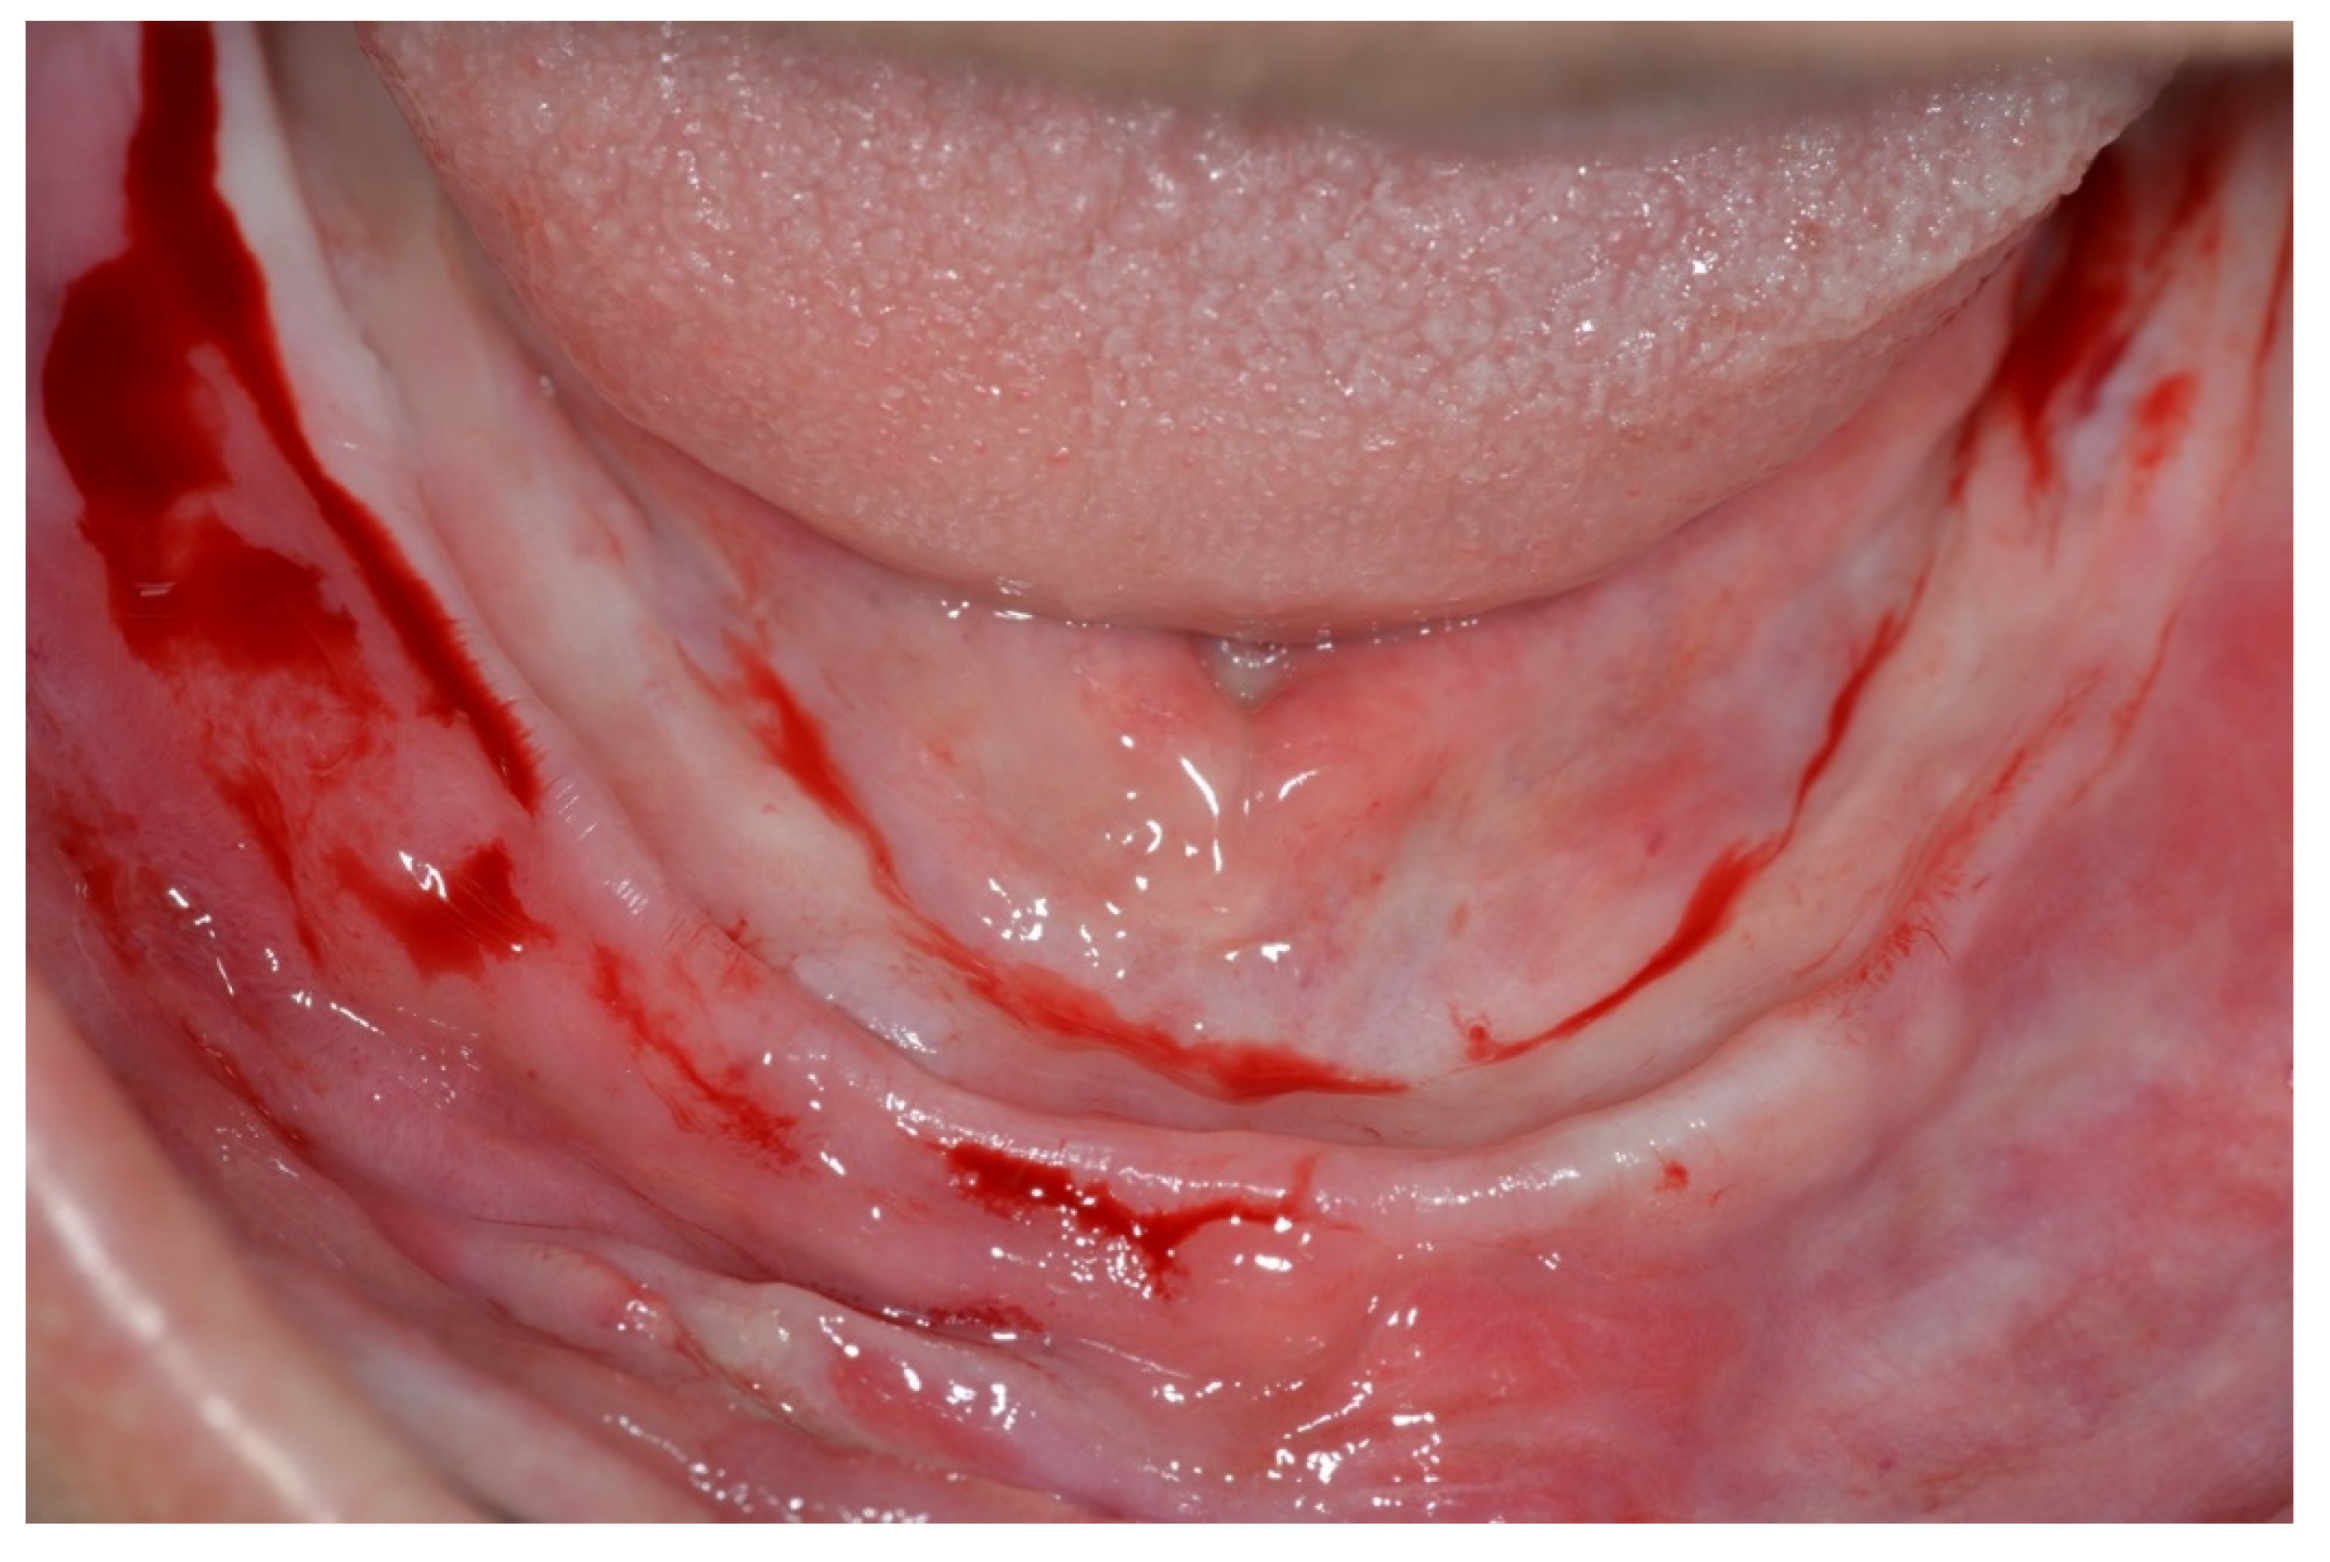

Surgical Protocol